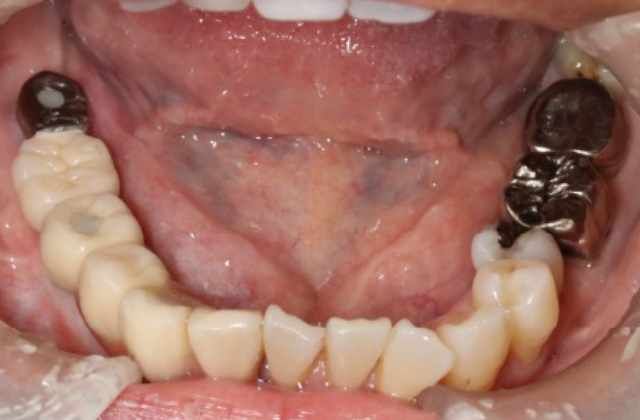

当科では、口腔内や顎骨内に発生する良性腫瘍、嚢胞性疾患に対し手術を行っています。ともに無痛性に緩慢な増大を特徴とするため、発見された際には顎骨の広範囲におよび、歯根吸収や下顎管の圧排を伴っている症例も少なくありません。特に若年者の顎骨腫瘍(嚢胞)の場合、顔貌の変形や下歯槽神経の損傷に配慮し、まず初期治療として開窓を行い、病変の縮小と骨新生を確認後に摘出を行います。ただし、エナメル上皮腫などの再発率の高い病変に対しては、一期的に顎骨切除を行うとともに、腸骨や腓骨を用いた硬組織再建を積極的に行っています。その際は術前にCT撮影を行い、3D画像によるモデルサージェリーを基にオーダーメイドのプレートを作製し、確実かつ迅速な手術を行っております。